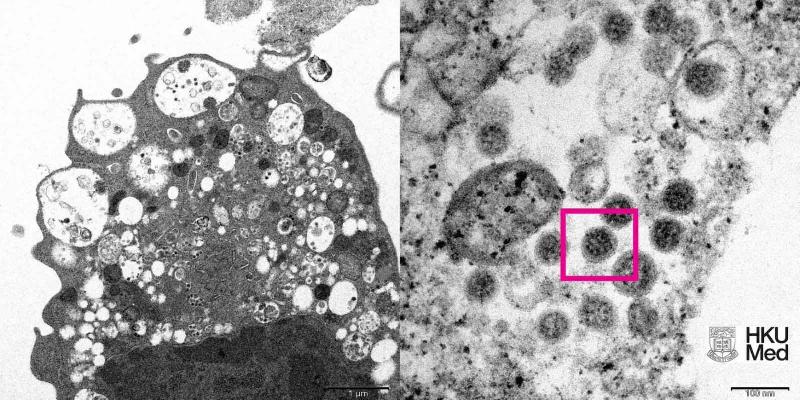

(圖左)低倍電子顯微鏡下感染新型冠狀病毒Omicron變異株後的猴腎細胞(Vero E6)。照片顯示細胞受損,腫脹囊泡,囊泡內含有黑色小病毒顆粒;(圖右)高倍電子顯微鏡下受感染的Vero E6細胞。照片顯示病毒顆粒,其表面呈現皇冠形的刺突蛋白(見紅框)。(香港大學醫學院供圖) 此外,SINOVAC科興與香港大學袁國勇院士團隊已簽訂合作協議,引進港大分離的奧密克戎變異株樣本,並於12月9日下午運抵北京,轉入中國醫學科學院醫學實驗動物研究所P3實驗室開展研究。 獲得新冠病毒奧密克戎變異株後,SINOVAC科興可更好地保障疫苗交叉中試驗和疫苗毒種篩選等研究開展,從而了解奧密克戎變異株對現有新冠疫苗的影響,並進而評價研製新冠病毒奧密克戎變異株疫苗的必要性。 SINOVAC科興具備成熟的新冠疫苗生產工藝和大規模生產能力,此前已開展了針對新冠病毒伽馬(Gamma)株和德爾塔(Delta)變異株新冠滅活疫苗研製工作。在新的奧密克戎變異株帶來新挑戰的背景下,SINOVAC科興也做好了開發新疫苗的所需準備,如有需要可快速推進新疫苗的研製和大規模生產工作。 【編輯:石欢欢】